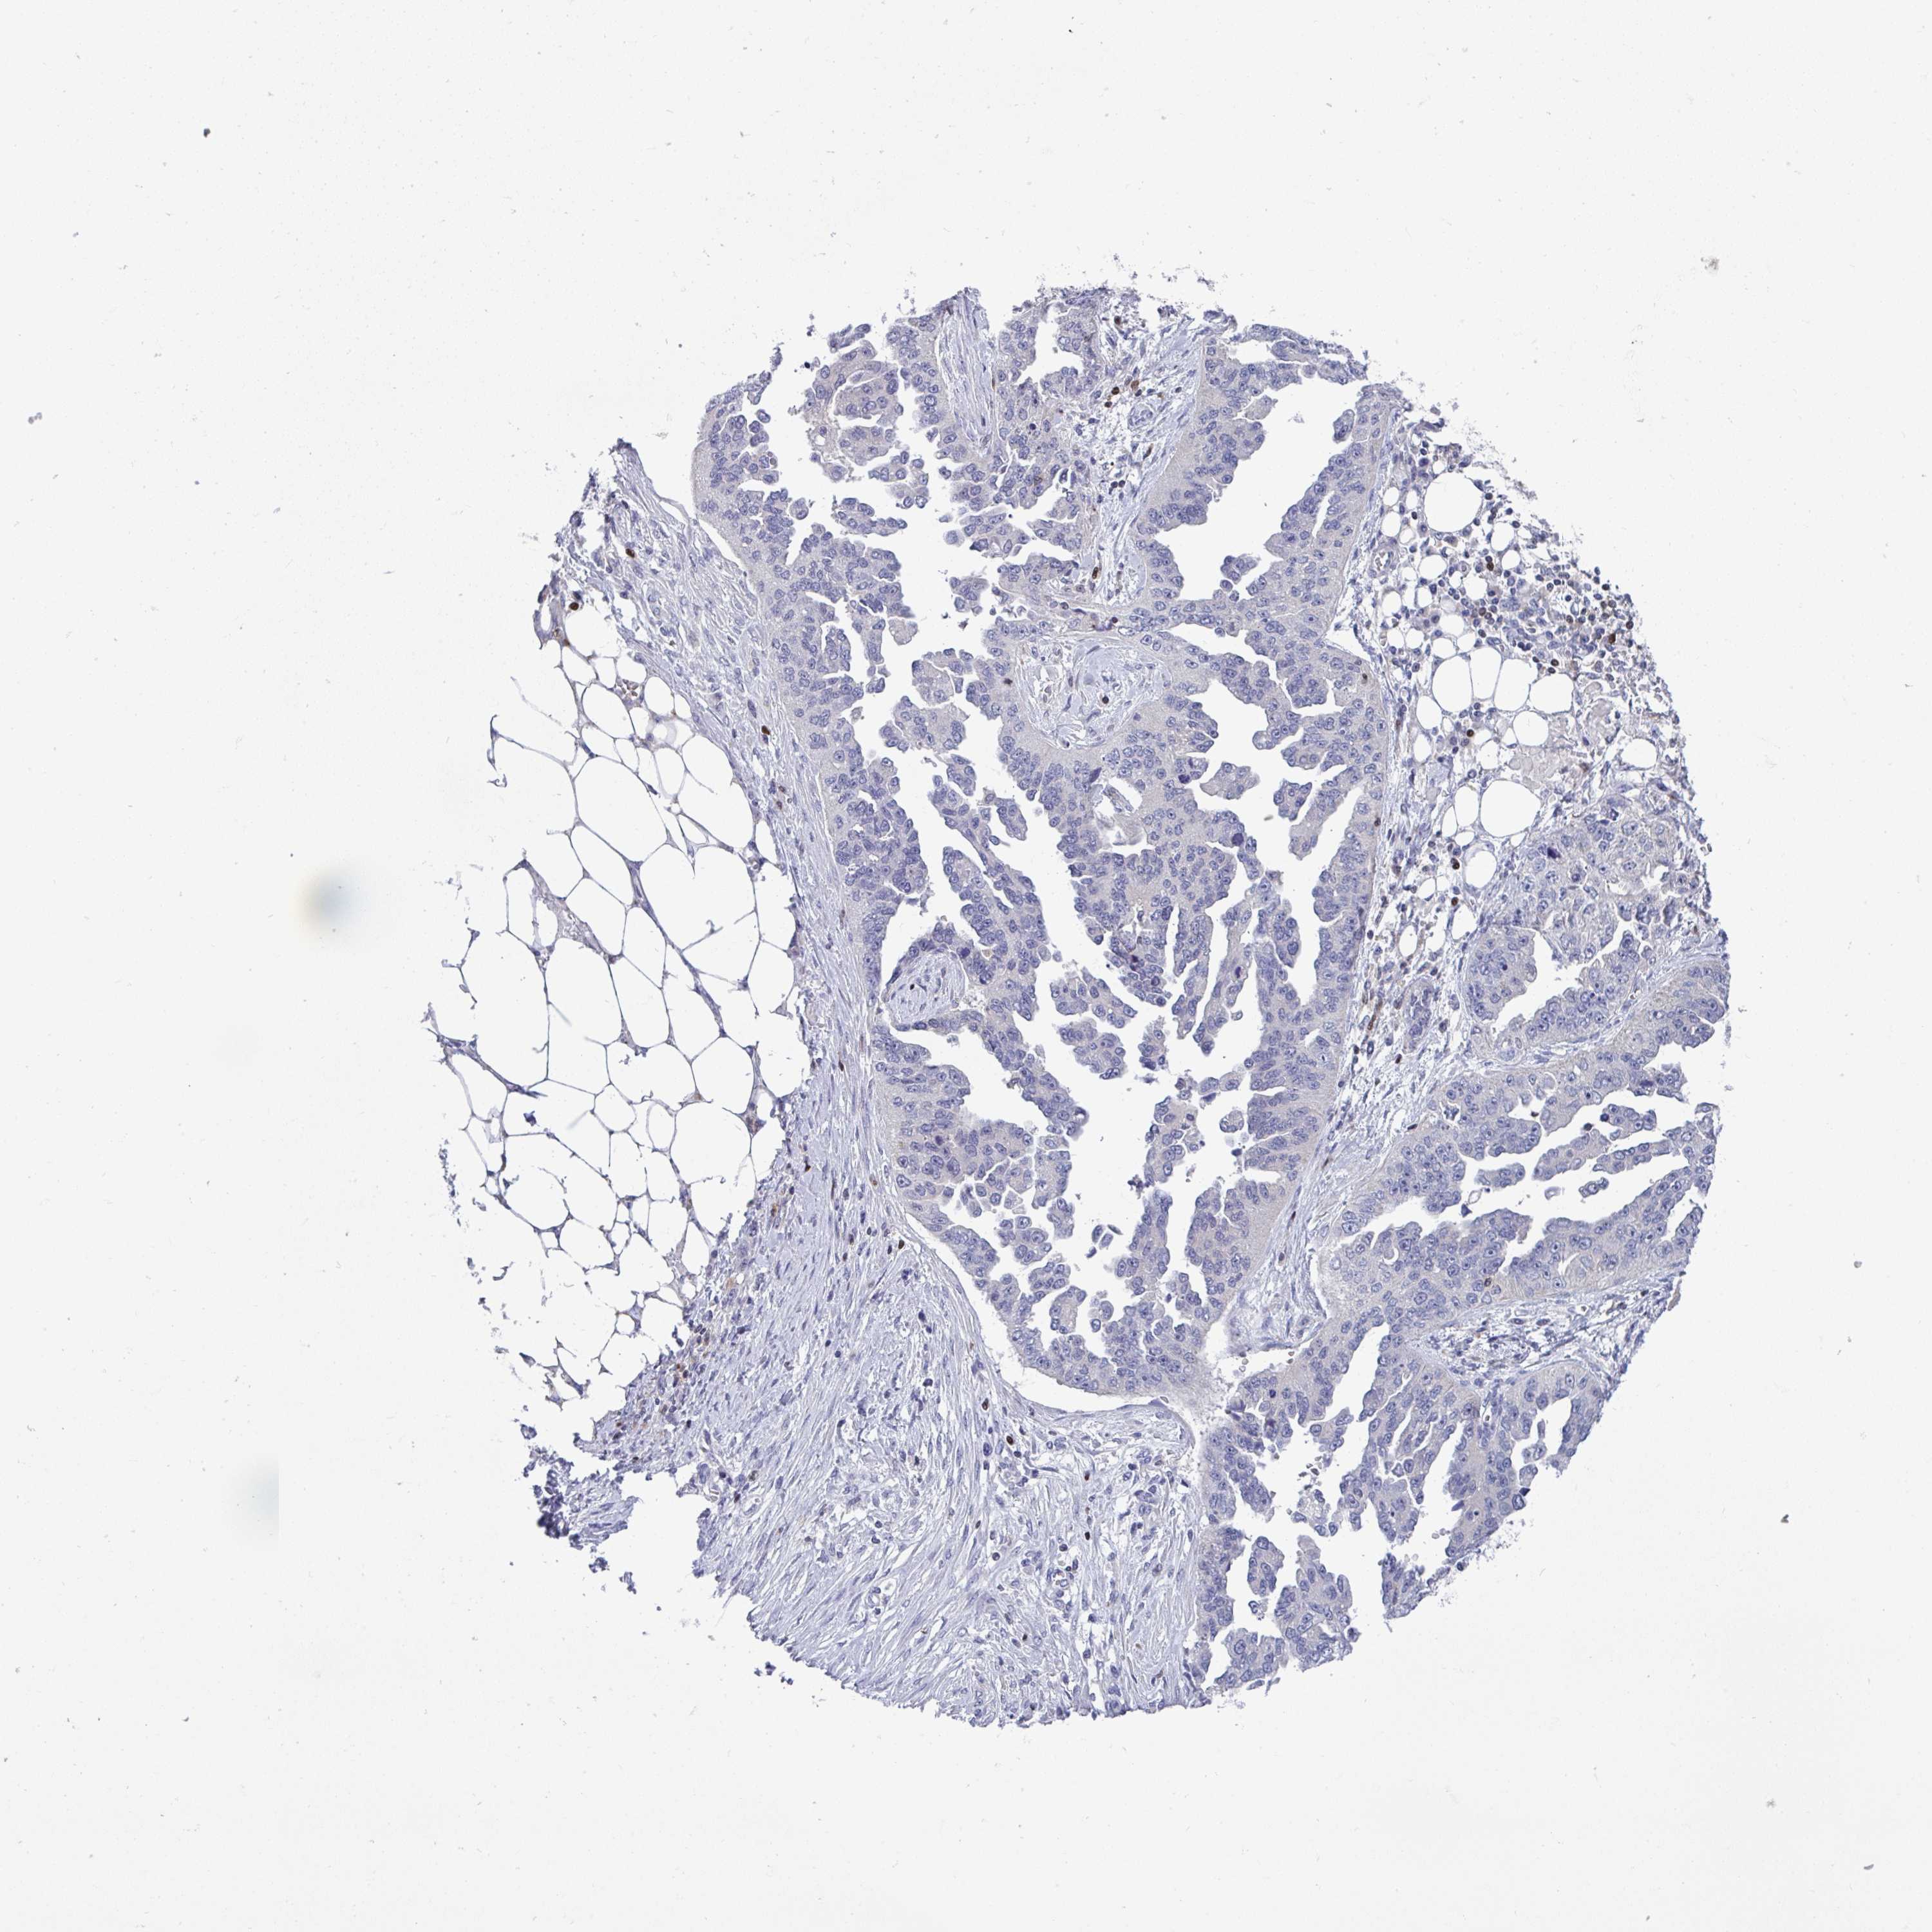

OVARIAN CANCER - Protein expressioni

A mouse-over function shows sample information and annotation data. Click on an image to view it in a full screen mode. Samples can be filtered based on level of antibody staining by selecting one or several of the following categories: high, medium, low and not detected. The assay and annotation is described here.

Note that samples used for immunohistochemistry by the Human Protein Atlas do not correspond to samples in the TCGA dataset.

Antibody stainingi

Antibody staining in the annotated cell types in the current human tissue is reported as not detected, low, medium, or high, based on conventional immunohistochemistry profiling in selected tissues. This score is based on the combination of the staining intensity and fraction of stained cells.

Each image is clickable and will lead to virtual microscopy that enables deeper exploration of all samples and also displays staining intensity scores, fraction scores and subcellular localization as well as patient and tissue information for each sample.

Antibody HPA057779

Cystadenocarcinoma, serous, NOS

Cystadenocarcinoma, mucinous, NOS

Carcinoma, endometroid